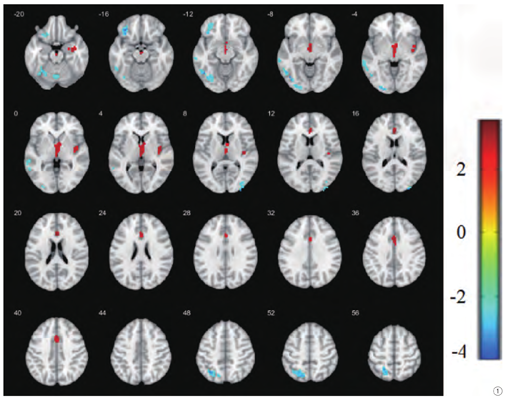

与治疗前比较,针刺治疗后MCI患者ALFF值增高的脑区有右侧海马旁回、左侧丘脑、右侧岛叶、左侧前扣带回(见表2,图1);ALFF值减低的脑区有左侧小脑后叶、左侧颞下回、右侧颞下回、左侧额下回、左侧颞中回、左侧枕下回、左侧顶上小叶(见表3,图1)。

注:图中红色表示ALFF值增高的脑区,蓝色表示ALFF值减低的脑区。

Note: In the figure, red indicates the brain area with increased ALFF value, and blue indicates the brain area with decreased ALFF value.